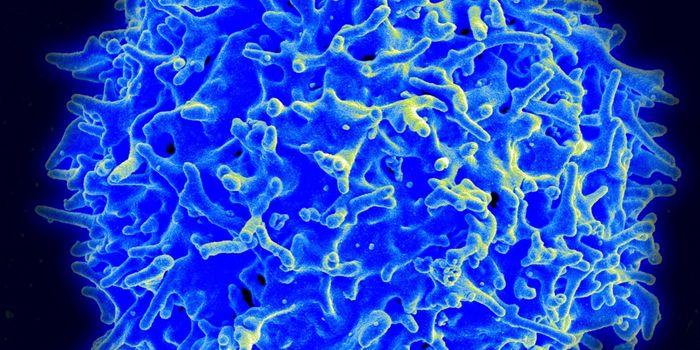

AUG 24, 2020ImmunologyOnce in the body, HIV tracks down T cells that bear the CD4 receptor. It attaches to these immune cells, fusing itself w ...